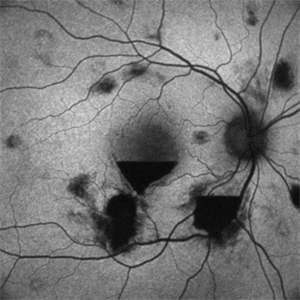

PROLIFERATIVE DIABETIC RETINOPATHY

EARLY PHASE FLUORESCEIN ANGIOGRAPHY OF A 50 YEAR OLD MALE WITH PROLIFERATIVE DIABETIC RETINOPATHY

Photographer: Dr. Akansha Sharma-Retina Foundation, Ahmedabad

Condition/keywords: florid type PDR, proliferative diabetic retinopathy (PDR)

LATE PHASE FLUORESCEIN ANGIOGRAPHY OF A 50 YEAR OLD MALE WITH PROLIFERATIVE DIABETIC RETINOPATHY